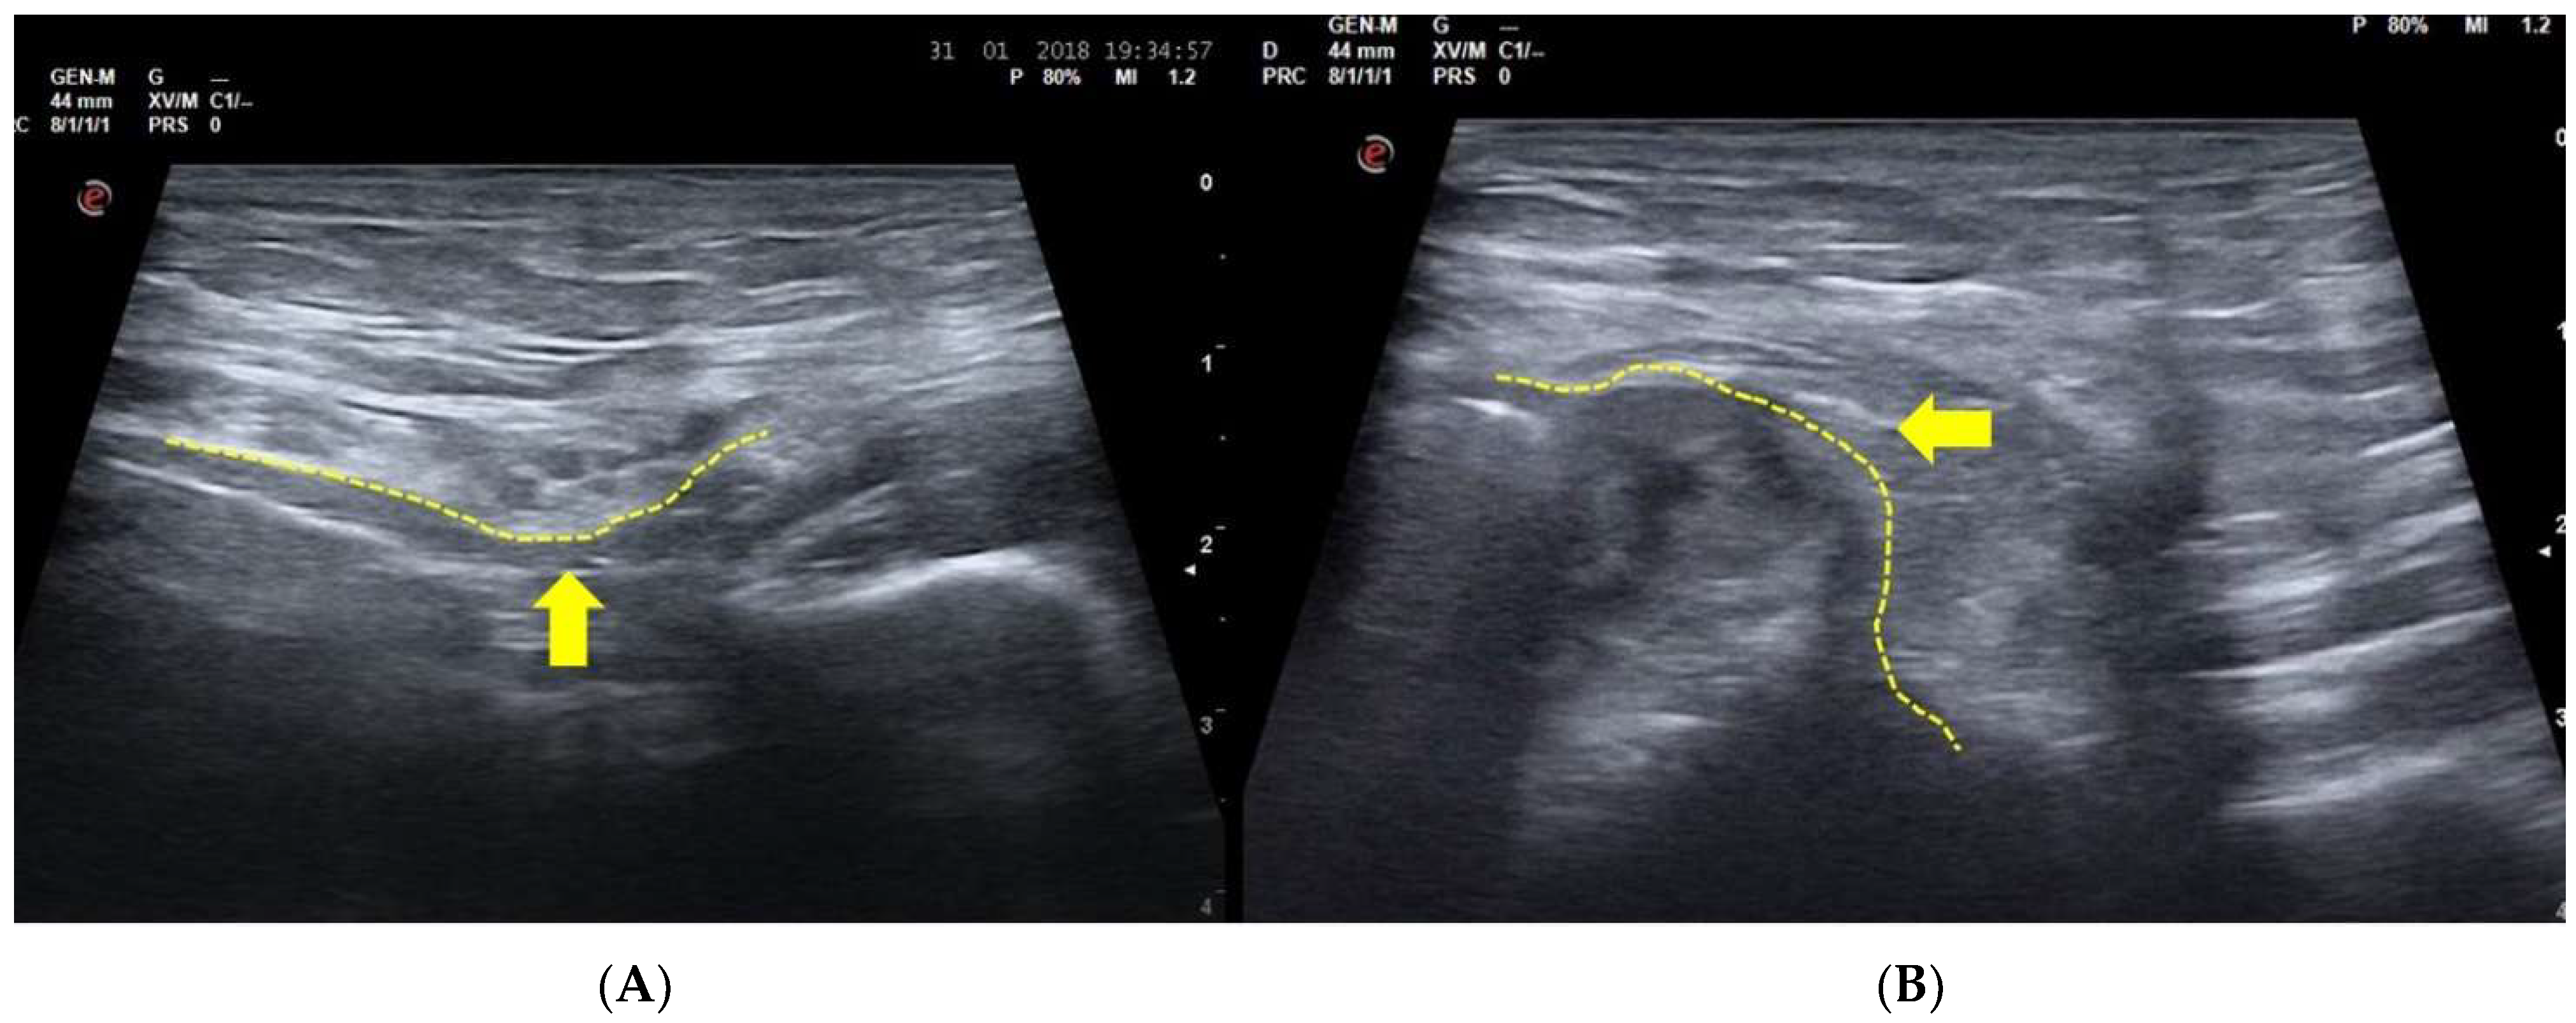

3.2. Dynamic Ultrasonography Examination